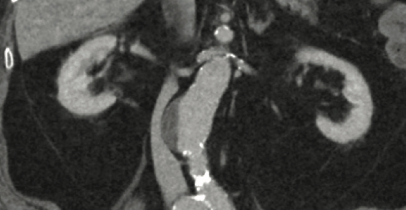

Urinalysis results were suggestive of urinary tract infection. Computed tomography scans of the abdomen/pelvis were obtained